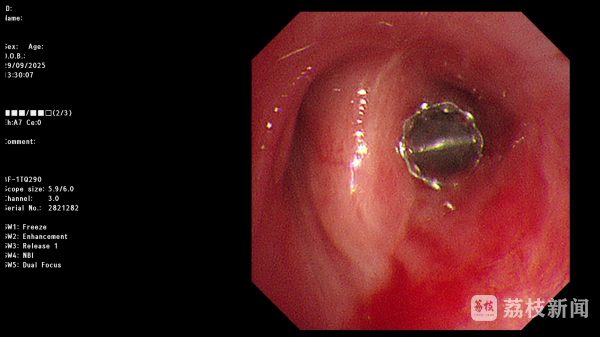

在明确治疗方案并与患者及家属充分沟通后,丁明团队决定实施经支气管镜EBV活瓣封堵术。手术在气管镜引导下进行,根据术前测量的结果,术中仅通过气管镜工作通道便将输送导管准确送到目标支气管,然后推动推送器将一枚直径4毫米的活瓣精准置入右上叶后段支气管开口。

这枚形似“鱼嘴”的活瓣暗藏玄机:它能随呼吸周期实现单向闭合,吸气时严密关闭阻止气体进入瘘口区域,呼气时则自动打开允许气体排出,形成“只出不进”的气流模式,从而维持胸腔负压,为瘘口愈合创造条件。置入瞬间,医护人员便观察到引流瓶水柱停止波动——这意味着漏气已即刻终止。